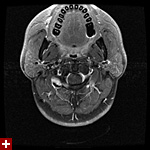

once i got back home and checked out my scans in osirix (the mac os x application to view DICOM medical imaging slides), i was blown away. talk about invasive: you haven't seen intimate until you've looked at photos of the inside of your body. the coolest part is since the scans were done in cross-sections, i can animate the scans so it looks like the beam is passing through my neck and head (all 800+ images). i've always known that inside my body was all sorts of muscles and veins and organs, but i guess i was hoping for something less messy, maybe circuit boards and memory chips instead. i know MRI's were first used in the late 60's, but this is my first time experiencing the technology in-person and it's pretty amazing. talk about futuristic! to be able to see with so much detail the insides of my body without having to cut me open! if scientists can do this, what else can they do? my only regret is they only imaged me from my shoulder up. i'd love to have a full-body scan. maybe i can fake some sort of internal injury and get my doctor to okay the procedure. i recommend anyone who's never had an MRI done to do so when they have the chance.

speaking of doctors, the main reason why i was at MGH this morning was for a follow-up appointment with my doctor. he basically told me that my MRI scans were fine as well as my blood work (he wrote me a letter a few weeks ago, so i already knew the news). since the pain in my neck had already disappeared,